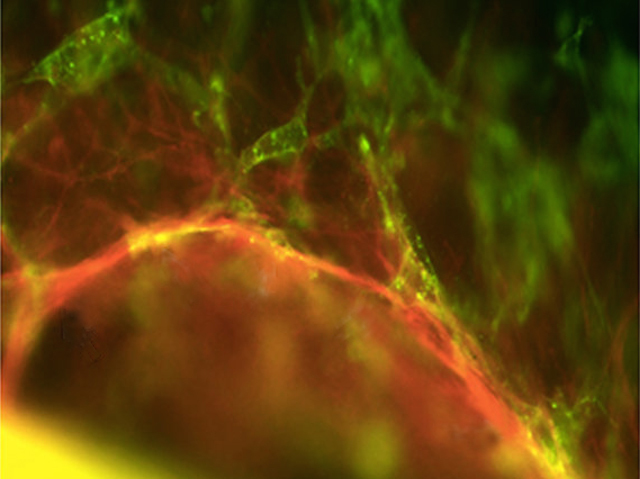

Heart failure affects over 900,000 people in the UK. It occurs when the muscle in the heart weakens, and fails to pump a sufficient amount of blood around the body. In situations like this, engineering new heart muscle in a laboratory could substitute damaged tissue; however, a barrier to its success has been the ability to grow an intricate network of blood vessels to support the growth and development of the new tissue. For the first time, researchers recently managed to manipulate endothelial progenitor cells obtained from blood to generate a 3D network of blood vessels to heart muscle cells (green fluorescence) within a gel derived from blood platelets. The gel also contained many different growth factors, allowing existing blood vessels to form links (red fluorescence) with the newly generated blood vessels. Building on this technique could lead to great progress in the field of regenerative medicine.